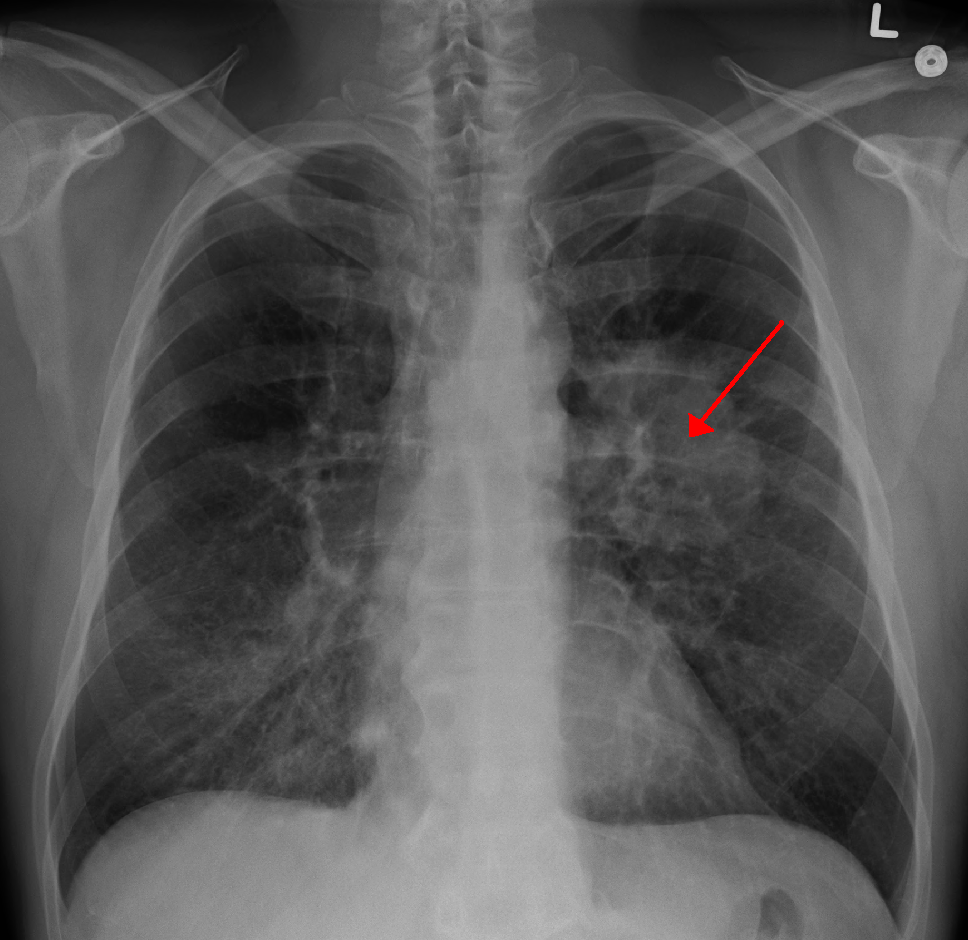

Theo đó, Dịch vụ Y tế Quốc gia Anh (NHS) kêu gọi những người có các triệu chứng như ho dai dẳng kéo dài hãy đi khám sớm, bởi theo các chuyên gia y tế, việc phát hiện bệnh sớm giúp ích cho quá trình điều trị bất cứ loại ung thư nào. Ảnh: Wikipedia.

Đặc biệt là bệnh ung thư phổi rất khó phát hiện trong giai đoạn đầu. Ảnh: SCC.